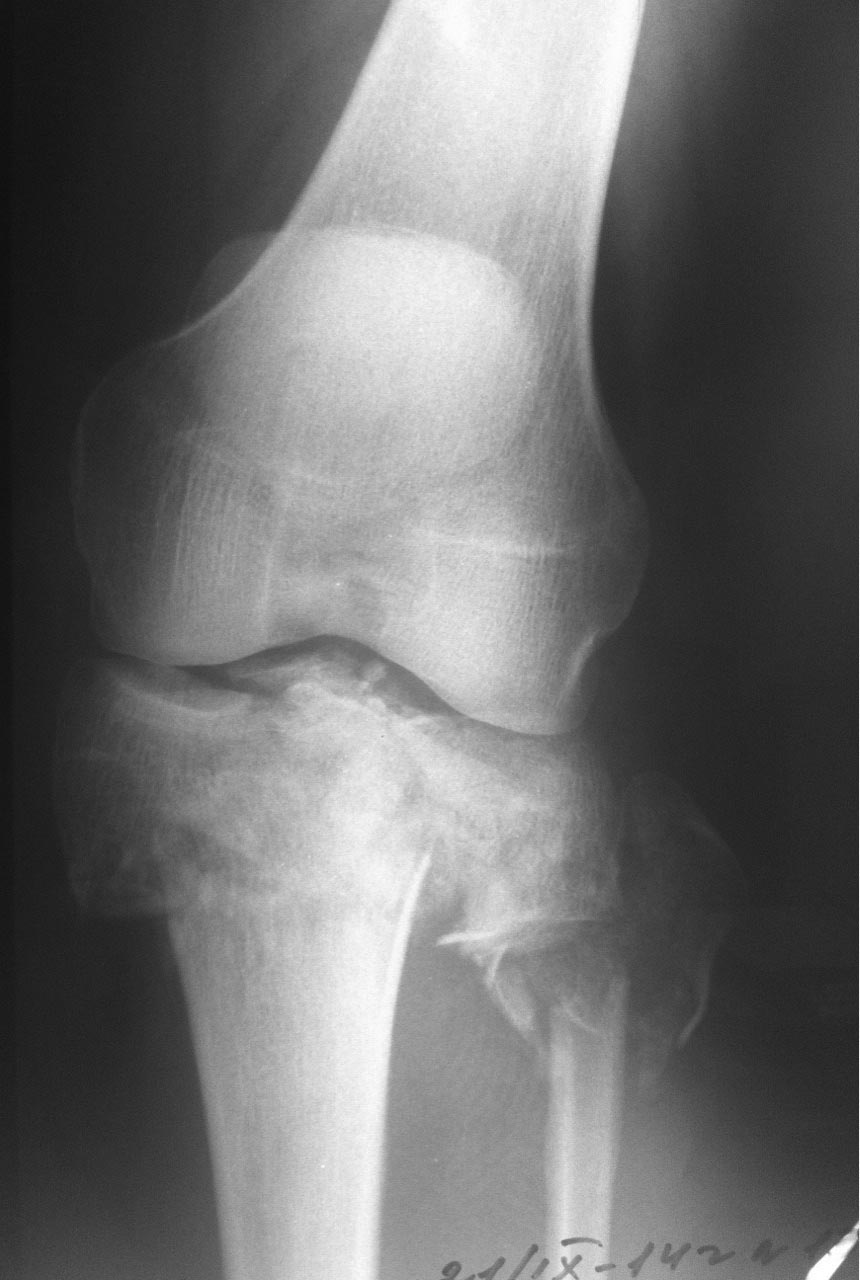

Мужчина 42 года. Травма 5 дней назад, спрыгнул с ж/д платформы (высота порядка 3-4 метров).

Планируется открытая репозиция и остеосинтез 2-мя пластинами. Ну и конечно же пластика костным трансплантатом. Возникла делема, из какого доступа будет лучше работать? А может из 2х? Уже устали спорить и доказывать друг другу свою правоту. Прошу у сообщества помощи..... А какой доступ сделали бы Вы?

Интересная постановка вопроса с Шацкер 6 на 5-е сутки.

Здесь сложный перелом тибиал плато в результате травмы с высокой энергией. На интересующие вопросы ответ можно найти в прежних разборах или на сайте форума, где имеются ссылки на множество книг с описанием современной тактики лечения, включая доступы. Но без прежнего опыта лечения сложных внутрисуставных переломов, такая короткая подсказка не всегда поможет добиться успеха. Кроме этого, одного желания помощь больному не хватает, надо своевременно предоставить запрошенный коллегами материал. Пассивность со стороны автора уменьшает интерес, и обсуждение теряет актуальность! Надеюсь, в этом случае доведем разбор до конца и дождемся результатов операции...

КТ срезы - не ради красоты изображения, а для определения топографии фрагментов! Доступ удобен на верхушке фрагментов, где легко делать репозицию и адекватную фиксацию. С количеством доступов до КТ можно не гадать, только на основании КТ можно определить направление доступа!

Внутрисуставные переломы не терпят долгих бездействии, а решение надо принимать срочно, обычно в день поступления. Стандартные рентген снимки в двух проекциях, и повторить после дистракции. КТ рекомендуется после дистракции! Дистракцию лучше делать наружным фиксатором, но при отсутствии можно на скелетном вытяжении. На вопрос дистрагировать или нет, может ответить характер перелома. При переломах с вовлечением обеих колонн надо делать дистракцию, а перелом одной колонны имеет исключение. Чрезмерный вальгус или варус требуют восстановления оси наружным фиксатором, а небольшие деформации можно оставить на короткое время на шине (knee Immobilizer brace), потому что вторая колонна удерживает от укорочения.